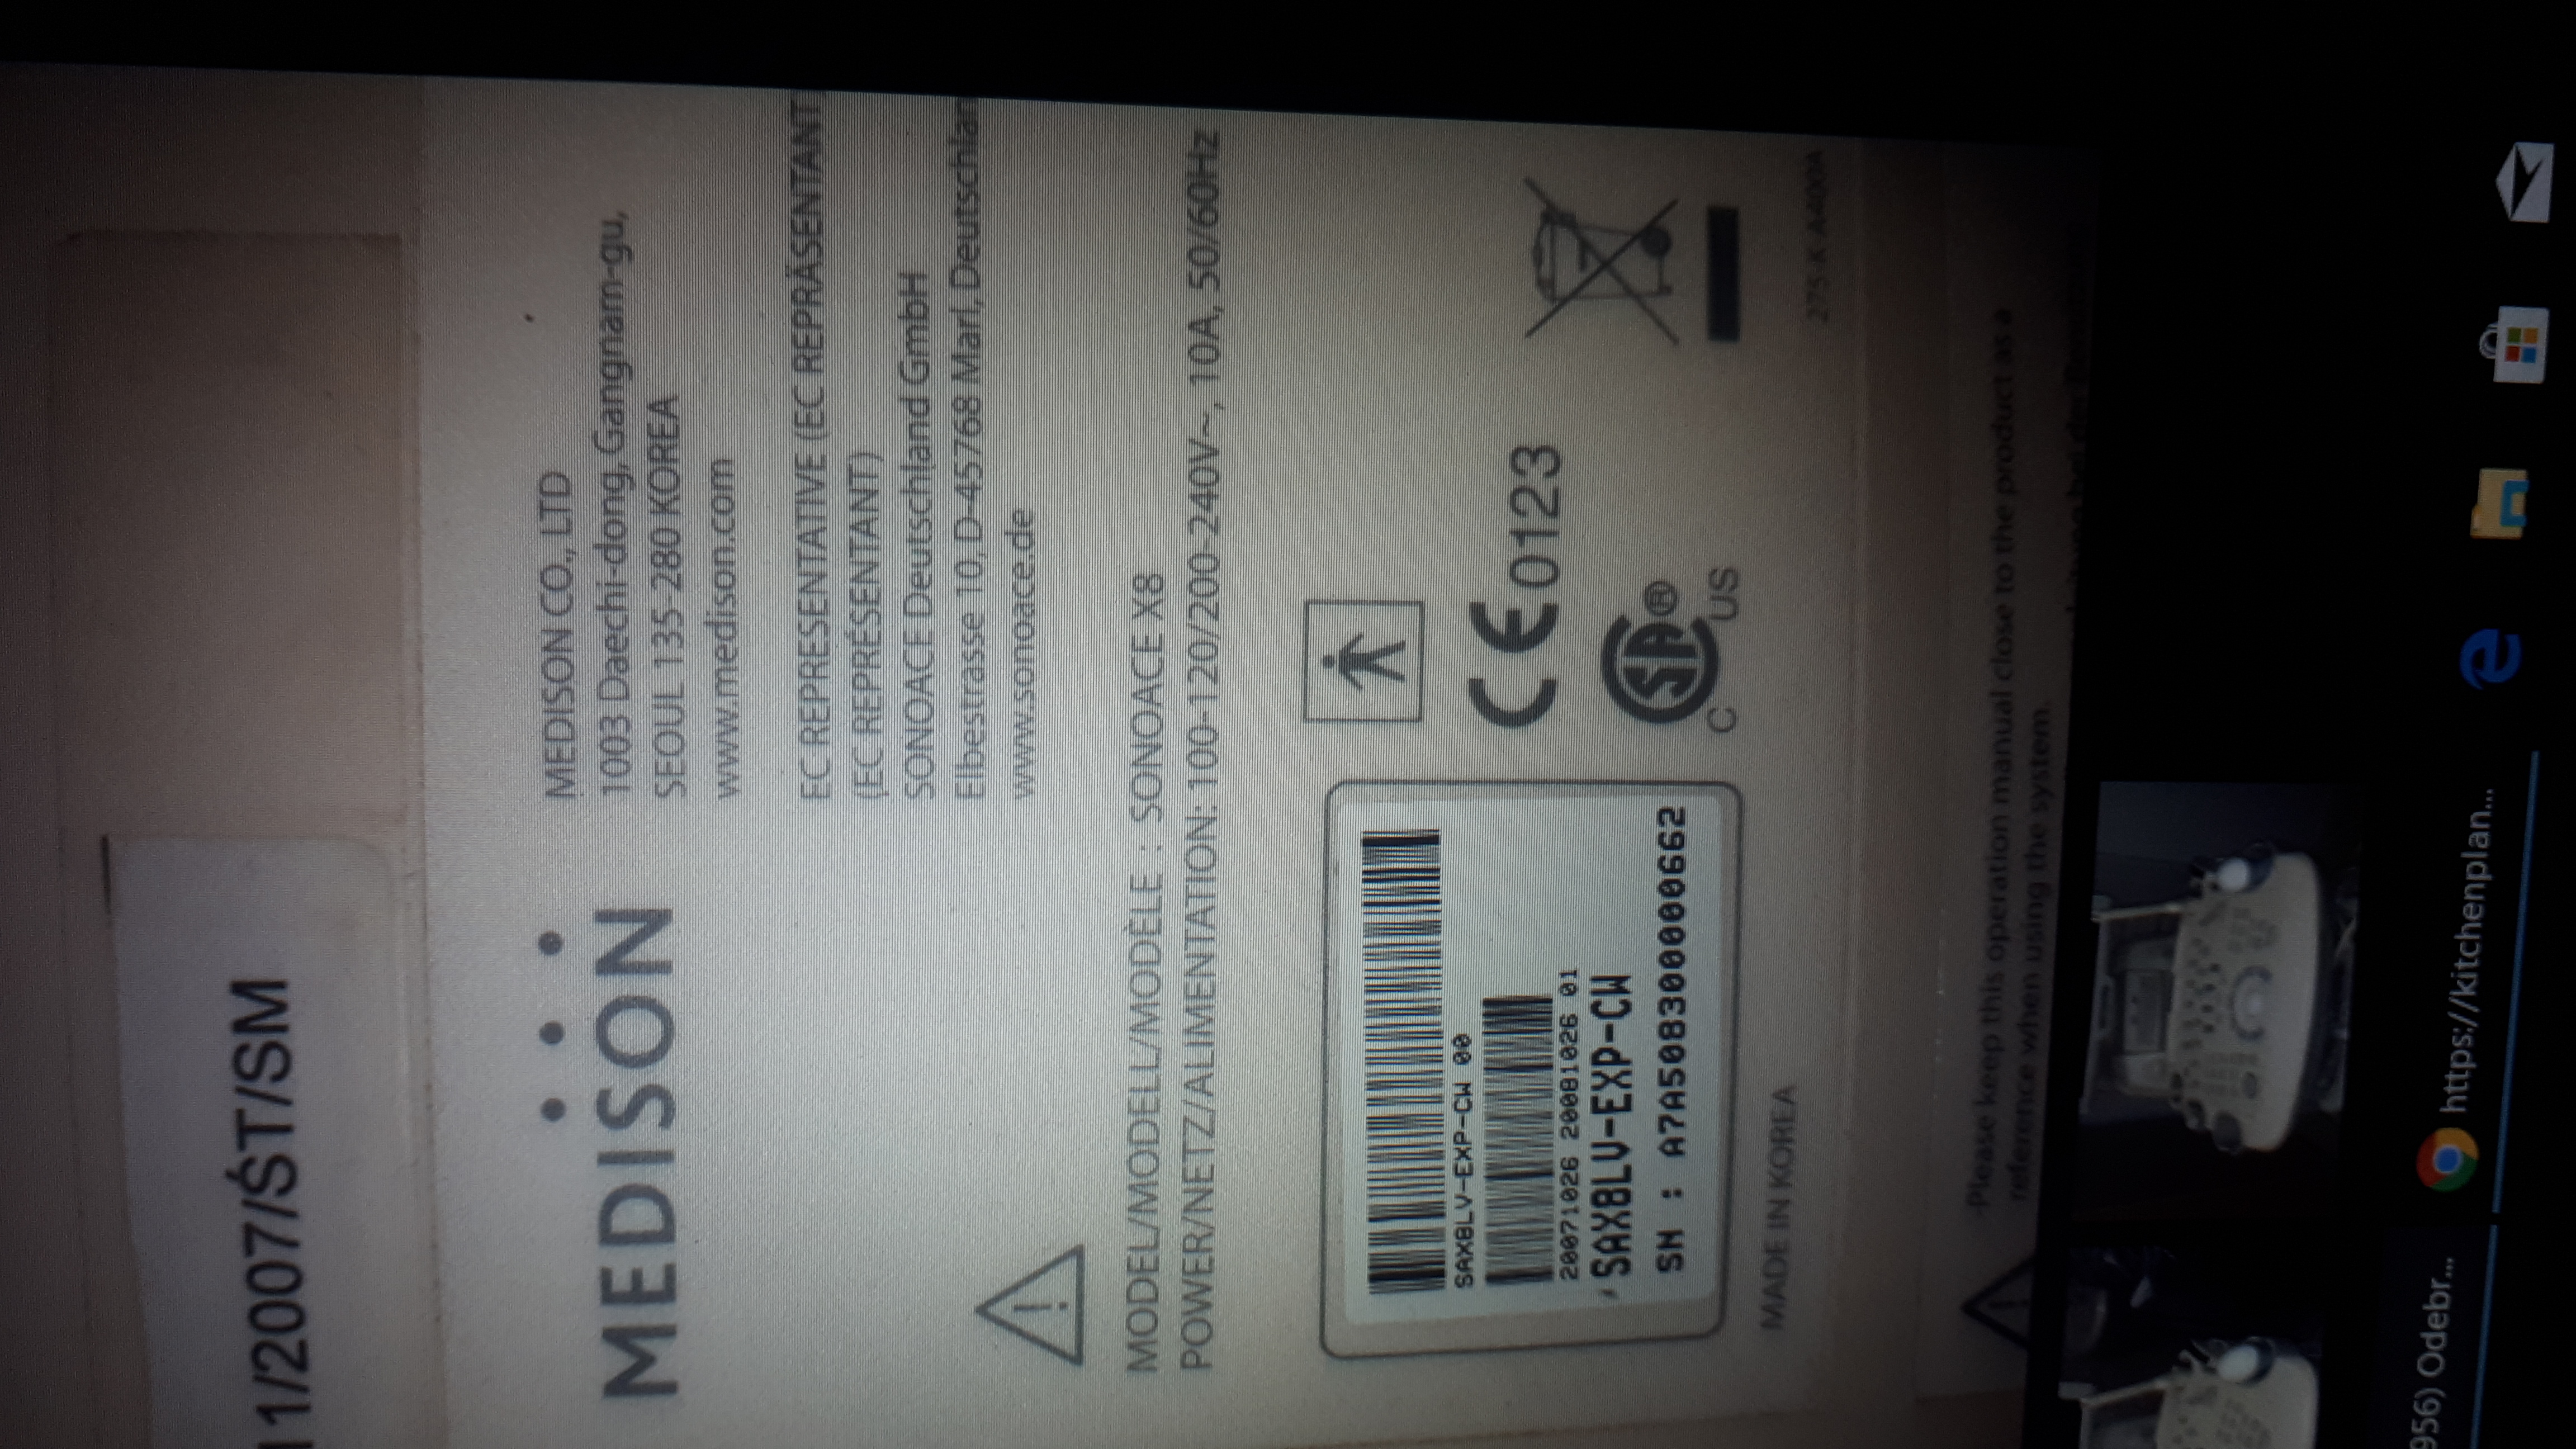

Posiadam do sprzedaży Aparat MEDISON SONOACE X8 z 4 sondami convex, endowaginalną, volumetryczną i liniową. Z funkcją Collor Doppler,Power Doppler ,Doppler pulsacyjny, z wbudowanym printerem Mitsubishi , Dodatkowo wgrany program kardiologiczny oraz pokrowiec i papierowa instrukcja obslugi : pełna

Rok produkcji 11.2007. Użytkowany od 2008 roku, 2x w tygodniu w prywatnym gabinecie ginekologicznym.